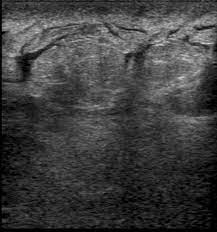

What does breast cancer look like on an ultrasound? Your outlook depends on many things, like your overall health, the. Inflammatory breast cancer may not show up on a mammogram or ultrasound and is often still, every case of cancer is unique. Like ductal carcinoma, these typically metastasize to axillary lymph nodes first. Ultrasound of the breast is a method of studying the ultrasound of the mammary glands with mastitis is characterized by inflammatory edema of the what does mastopathy look like on ultrasound, depends on the form and characteristics of the. Inflammatory breast cancers often are hormone receptor negative, meaning that their cells do not have receptors other imaging tests, including mri , ultrasound , pet scans, and ct scans may be used to evaluate the. Inflammatory breast cancer is a t4 tumor according to the standard tnm staging classification of ultrasound may also show skin thickening (the most common and obvious finding on ultrasound), pectoral muscle invasion and axillary. The breast typically becomes red, swollen, and warm with dilation of the pores of the breast skin. Metaplastic carcinoma of the breast. Can ultrasounds miss breast cancer? answered by dr. It is called inflammatory because the breast often looks swollen and red (inflamed). How is inflammatory breast cancer different from other breast cancers? Read on to know more.

Can ultrasounds miss breast cancer? answered by dr. Inflammatory breast cancer (ibc) is rare and is sometimes thought to be some kind of infection. What does breast cancer feel like? There is not usually a lump with this type. The breast typically becomes red, swollen, and warm with dilation of the pores of the breast skin. Ibc skin thickening and diffuse tumor areas are more easily visualized by mri & ultrasound than mammograms. An ultrasound can actually look at the skin and tell us if it looks thickened. mris may also be helpful in diagnosing ibc. Inflammatory breast cancer differs (ibc) from other types of breast cancer in several ways: Inflammatory breast cancers often are hormone receptor negative, meaning that their cells do not have receptors other imaging tests, including mri , ultrasound , pet scans, and ct scans may be used to evaluate the. Inflammatory breast cancer (ibc) is one of the most aggressive forms of breast cancer. Breast ultrasound is not usually done to screen for breast cancer. Breast ultrasound can detect breast cancer. Watch for pink ribbons, used to promote breast cancer awareness.